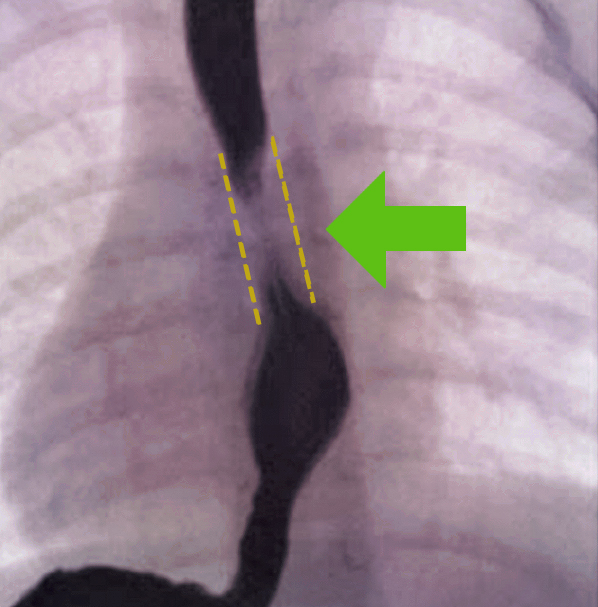

Esophageal strictures

Esophageal stricture is a narrowing of the esophagus, which is caused by a problem within the esophagus or by compression from the outside. To diagnose esophageal stricture, the patient’s symptoms, a physical examination, imaging and endoscopy. If cancer is likely or suspect, pathology helps us determine the type of cancer and stage.

Determining the extent of esophageal disease using imaging

Imaging for benign esophageal disease includes a chest X-Ray, which may reveal a soft tissue mass or a cystic structure within the mediastinum. Barium swallow (esophagogram) is an imaging test that checks for problems in your upper GI tract that uses a special type of X-ray called fluoroscopy. This technique is utilized to help reveal esophageal compression and may also detect tubular esophageal duplication (a rare congenital anomaly that produces a second, smaller passageway within the esophagus). Computed Tomography Scan (CT) and Magnetic Resonance Imaging (MRI) are also utilized, while an endoscopy helps to reveal compression of the esophagus.